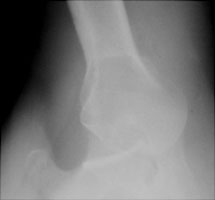

- Click on the image for a larger versionAAP radiograph of the right shoulder. A cursory examination reveals no obvious dislocation.